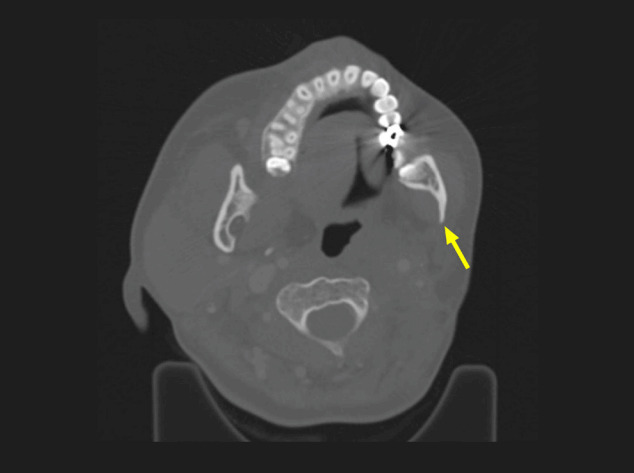

This study aimed to evaluate the long-term efficacy and complication of radiotherapy for benign soft tissue tumors. Five cases of benign soft tissue tumors (two plexiform neurofibromas, two juvenile nasopharyngeal angiofibromas, and one cavernous sinus hemangioma) who underwent radiotherapy were enrolled. All patients had at least 10 years of follow-up. The median follow-up duration was 12 years (range, 10 to 27). Three patients underwent incomplete excision prior to radiotherapy. Radiation doses were either 54 Gy in 30 fractions or 50.4 Gy in 28 fractions (1.8 Gy per fraction). Every patient achieved complete remission (CR) or near-CR. The tumor volume decreased significantly within the first 2 years of follow-up and continued to decrease slowly up to 10 years; no distinct further decrease in tumor volume was observed after 10 years. One patient developed left mandibular hypoplasia 8 years after radiotherapy. Significant volume decrease was achievable within a few years after radiotherapy in benign soft tissue tumors. Therefore, radiotherapy is a viable option for unresectable or incompletely resected benign soft tissue tumors with a minimum risk of complication.

Abstract Image